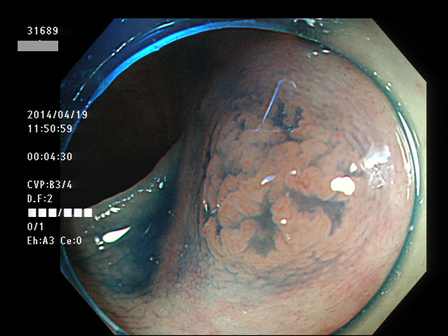

31600 31601 31603 31604 31606  31607 31610 31611 31612 31616 31623 31624 31625 31627 31630 31631 31632 31638 31639 31640 31641 31642 31644 31645 31646 31649 31650 31653 31656 31658 31659 31660 31661 31662 31665 31666 31667 31670 31671 31672 31673 31674 31676 31679 31680 31683 31684 31687 31689 31691 31693 31694 31696 31697 31699 ・・・・の55名

上記100名より抽出した平坦・陥凹型腺腫(=癌化の危険が高いが見落としやすい病変)の内視鏡写真